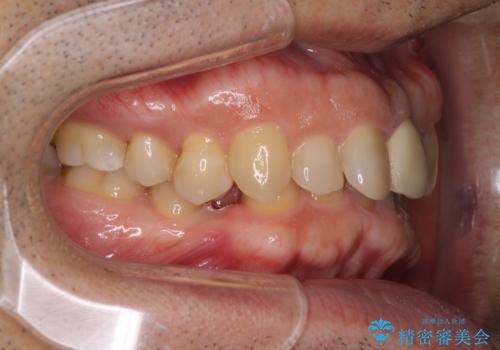

下顎は左右1本ずつ小臼歯が欠損しており、右側にはやや大きな欠損がありました。

欠損により下顎歯列は相対的に小さく、上顎に深く咬みこんでしまうディープバイトとなっていました。

咬合力が強く、インビザラインのみではディープバイトを改善することができず、半年間ほどワイヤー装置による矯正治療を行いました。

インプラントの埋入は矯正治療中に行い、矯正治療後はインプラント上補綴および、前歯のセラミック治療を行いました。